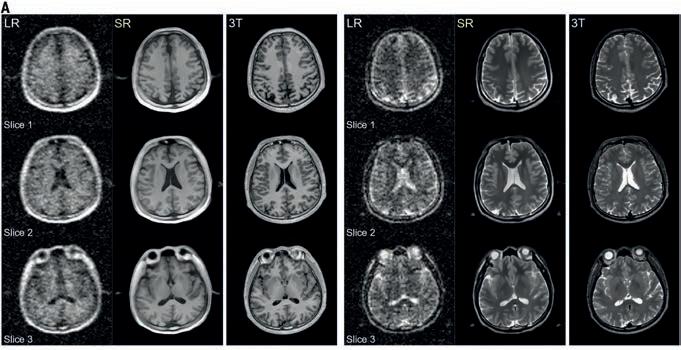

Atividade física medida por acelerômetro e idade cerebral orientada por neuroimagem

Fluxo de trabalho do estudo para investigar as associações das quantidades de PA de intensidade leve (LPA), PA de intensidade moderada (MPA) e PA de intensidade vigorosa (VPA) medidas por acelerômetros com a idade cerebral

(A) O modelo de predição da idade cerebral é construído alavancando o treinamento do algoritmo LightGBM em 1.425 fenótipos derivados de imagem (IDPs) de ressonância magnética cerebral ponderada em T1 e idade cronológica. As características inicialmente passam por uma classificação de importância de características baseada em árvore, onde as 50 principais características importantes são selecionadas. Em seguida, a distância supervisionada entre cada característica é calculada e então submetida a agrupamento de hierarquia para identificar grupos de características redundantes. Após remover a redundância, interpretamos visualmente o subconjunto final selecionado de características usando a técnica SHAP. Para lidar

Oexercício físico faz bem ao cérebro, mas só até certo ponto. Um novo estudo que acompanhou quase 17.000 pessoas usando monitores de atividade física de pulso revelou uma verdade surpreendente: tanto a pouca atividade física quanto o excesso de atividade física podem acelerar o envelhecimento cerebral. A pesquisa desafia a crença

com o viés, a idade cerebral prevista foi corrigida pelo método linear. (B) Primeiro, investigamos as correlações entre AP e BAG medidos objetivamente usando modelos não lineares e lineares. Em seguida, para obter insights sobre AP e estruturas cerebrais, investigamos as correlações entre AP e 1.425 IDPs usando modelos não lineares e lineares. (C) Para verificar se AP e saúde cerebral foram mediadas por BAG, conduzimos uma análise de mediação. Função cognitiva e distúrbios cerebrais foram selecionados como desfechos de interesse para a saúde cerebral. LightGBM, Máquina de Intensificação de Gradiente de Luz; SHAP, Explanações Aditivas de SHapley; AF, atividade física; LPA, AF de intensidade leve; MPA, AF de intensidade moderada; VPA, AF de intensidade vigorosa; MVPA, AF de intensidade moderada a vigorosa; BAG, diferença de idade cerebral

comum de que mais exercício físico é sempre melhor para a saúde cognitiva. Usando aprendizado de máquina avançado para analisar exames cerebrais, pesquisadores descobriram que quantidades moderadas de exercícios pareciam retardar o envelhecimento cerebral, independentemente do nível de intensidade. No entanto, pessoas que se exercitavam em excesso

apresentaram sinais de envelhecimento cerebral acelerado semelhantes aos daquelas que quase não se movimentavam. O estudo, publicada na Health Data Science, acompanhou os participantes por sete dias usando acelerômetros precisos que mediam atividades físicas leves, moderadas e vigorosas. Os pesquisadores então usaram inteligência artificial para prever a “idade

de predição da idade cerebral

(A) Seleção sequencial para frente a partir de um subconjunto selecionado de características após a remoção da redundância. O gráfico de linhas representa o MAE decrescente (eixo y esquerdo) mediante a inclusão de características, uma por iteração. O gráfico de barras exibe a importância decrescente das características com base na permutação (eixo y direito). MAE, erro absoluto médio. (B a E) Associações da idade cerebral e da diferença de idade cerebral com a idade cronológica antes e depois da correção. Os resultados são agregados a partir da validação cruzada de 10 vezes, onde as previsões de cada dobra foram geradas usando modelos treinados nas outras 9 dobras. Para correção de viés, os parâmetros foram estimados independentemente dentro de cada dobra de treinamento e aplicados à dobra de teste correspondente. Cada gráfico

cerebral” de cada pessoa a partir de exames de ressonância magnética e compará-la com sua idade cronológica real.

O que eles descobriram foi uma curva em forma de U: o envelhecimento cerebral acelerou em ambos os extremos do espectro de atividade física. Pessoas nas faixas intermediárias de atividade física apresentaram as idades cerebrais mais jovens em relação à sua idade cronológica. “Nosso estudo não apenas confirma uma relação não linear entre a ativi-

exibe um gráfico de densidade de kernel da idade cerebral, da diferença de idade cerebral plotada em relação à idade cronológica e das linhas de regressão linear e dos coeficientes de correlação de Spearman (r). (F) Distribuição dos valores de SHAP para as 27 principais características com base no maior valor médio absoluto de SHAP. Cada amostra no conjunto de teste é representada como um ponto de dados por característica. O eixo x mostra o valor SHAP e a codificação por cores reflete os valores das características. (G) Explicação individualizada da idade cerebral para um indivíduo de 64 anos. O valor de saída (a linha tracejada cinza com o número na parte superior do gráfico) mostra a idade cerebral prevista para esse indivíduo. O valor base (a linha tracejada cinza com o número na parte inferior do gráfico) aproxima-se da idade cronológica (ou seja, 64 anos). As características em vermelho aumentam a idade cerebral e as em azul a diminuem

dade física medida objetivamente e o envelhecimento cerebral em uma grande população, mas também fornece insights práticos: mais exercícios nem sempre são melhores — a moderação é fundamental”, disse o professor associado Chenjie Xu, da Universidade Normal de Hangzhou, que liderou a pesquisa.

A equipe utilizou um algoritmo de aprendizado de máquina chamado LightGBM para analisar mais de 1.400 medições cerebrais diferentes obtidas por ressonância magnética. Essa abordagem alcançou uma precisão notável, prevendo a idade das pessoas com uma diferença média de cerca de 3 anos — uma precisão que permitiu aos pesquisadores detectar diferenças sutis nos padrões de envelhecimento cerebral.